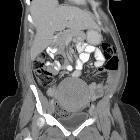

CT

A well-defined "collection" comprised of mixed gas and soft tissue is seen, often surrounded by free fluid and adjacent to other collections. The gas bubbles are arranged in linear patterns, and the collection has a geometric shape. An enhancing margin typical of abscesses is usually not present.